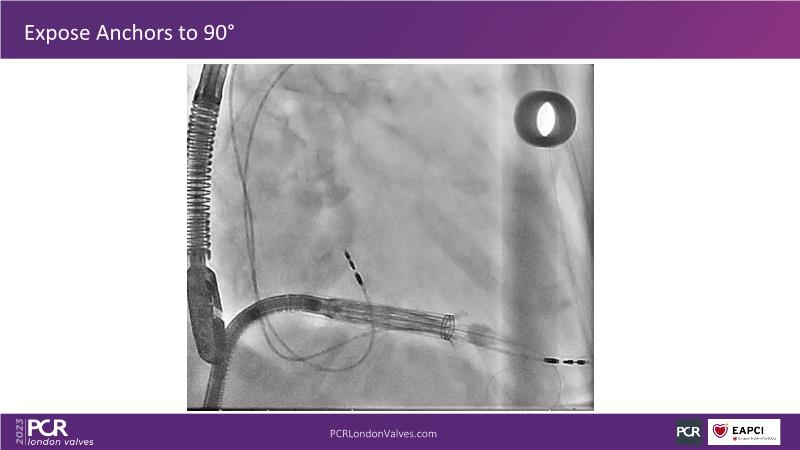

This session explores the features of the PASCAL Precision and the EVOQUE tricuspid replacement systems through simulators and case presentations, while a panel of experts discuss the technology, witnessing live demonstrations of treating mitral and tricuspid regurgitation patients.

- To introduce the EVOQUE tricuspid replacement system showcased with a simulator and a case presentation